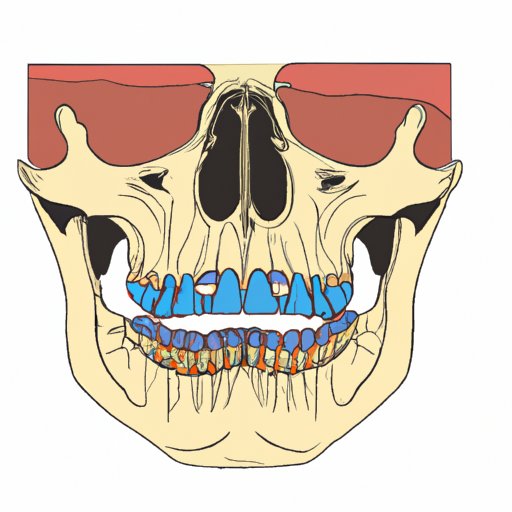

The Facial Bones that Form the Roof of the Mouth: Key Players and Unveiled Secrets

This article explores the anatomy and function of the facial bones that form the roof of the mouth, with a focus on the maxillary and palatine bones. It covers various aspects of the roof of the mouth, including injuries, conditions, fun facts, and treatment options